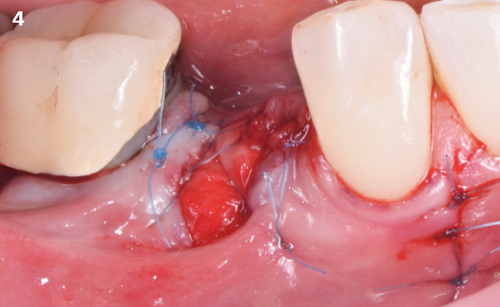

"After the extraction, I realized that the buccal wall was missing and I had to leave the membrane exposed. The regenerative potential of the site could be poor, so I decided to boost the biomaterials’ effect with polynucleotides and hyaluronic acid."

The Situation

The patient (45 years old, female, non-smoker, no previous pathologies) is referred for extraction of tooth 45 and immediate implant placement. The site showed an increased probing depth and a marked bone loss.